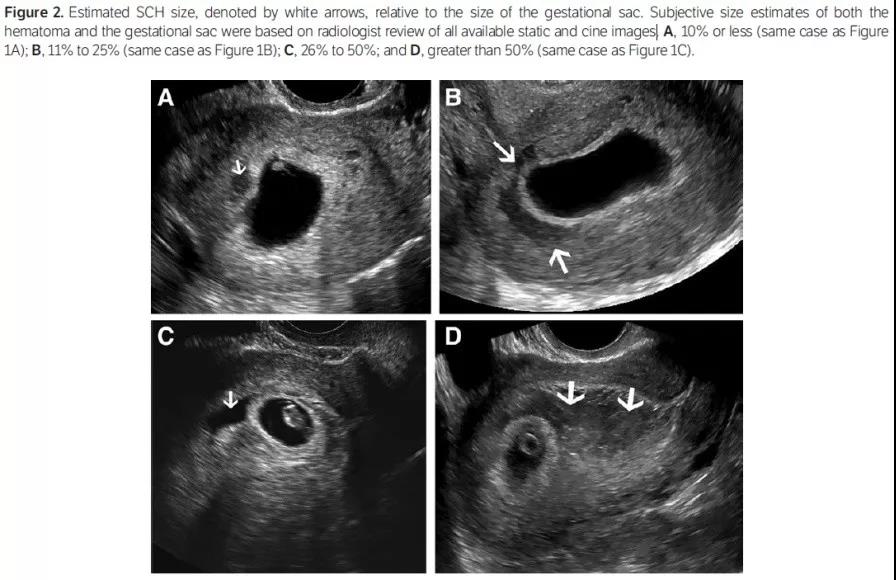

B超医生检查时,利用静态或动态的图像,估计血肿大小与孕囊大小的比值得到的评级更有临床意义。

血肿大小与孕囊大小的比值为:

≤10%,自然流产率为5.8%;

11%-25%,自然流产率为8.9%;

26%-50%,自然流产率为10.8%;

>50%,自然流产率为23.3%;